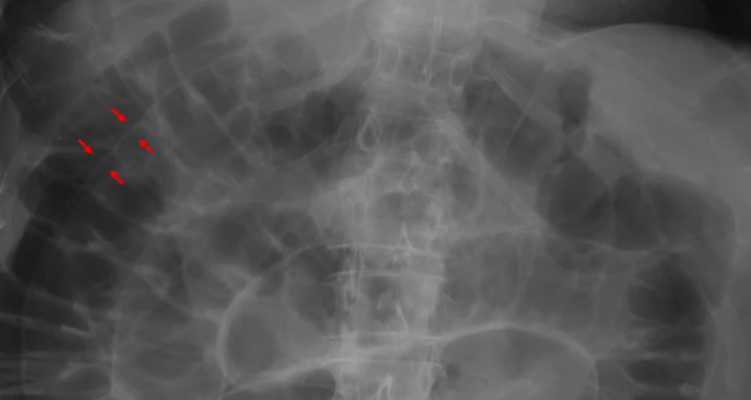

To what structure are the arrows pointing?

A) Intestinal walls

B) Stomach

C) Kidney

D) Liver

Correct Answer: